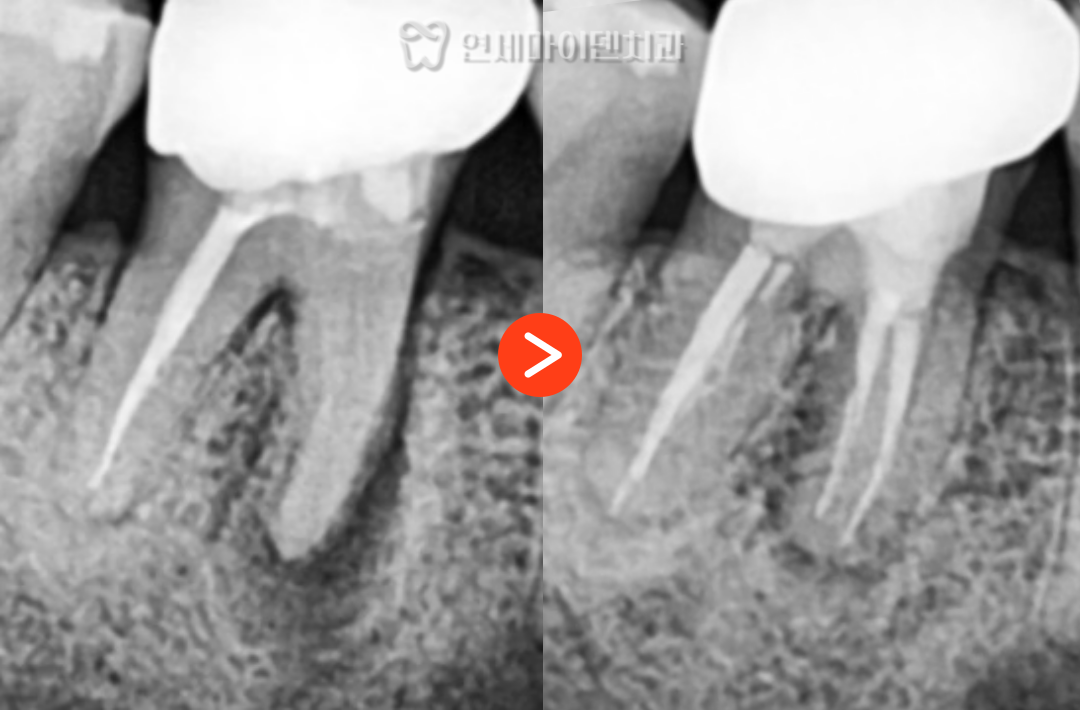

치료 직후 촬영한 엑스레이에서는 일부 뼈 손실이 보였지만,

명확한 크랙이 없었기 때문에

경과 관찰을 통해 회복 여부를 지켜보기로 했습니다.

1년 후 재검진 결과,

손실되었던 부위에 새로운 뼈가 형성되고

염증이 사라진 모습을 확인할 수 있었습니다.

✅ 치료 전후 비교

✔ 기존 신경치료에서 놓친 신경관 발견 및 치료

✔ 신경치료 후 1년 경과 관찰 결과, 뼈 재생 및 염증 해결